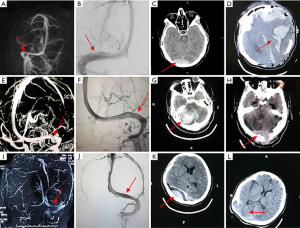

For early complications post-stenting, 4 patients (11.4%) in control group complicated with stenting-related subdural hematoma, all the hematomas located at the contralateral of the stenting side (Figures 1,2). Whereas, no subdural hematoma event (0.0%) occurred in perioperative management group, P=0.031. Other complications, such as stent-adjacent stenosis, intraluminal thrombosis, and intraluminal restenosis showed no statistic difference between the two groups.

Importance of strictly preoperative ICP control

In this study, 4 out of 35 patients in control group (11.4%) complicated with subdural hematoma, moreover, all of the hematomas located at the opposite side of the stent. However, no hematoma event occurred in the perioperative management group. The mechanism of the stenting-related contralateral side subdural hematoma was not clarified. A possible explanation for this phenomenon was that patients in the control group did not undergo a transiently strictly preoperative ICP reducing therapy. Therefore, we hypothesized that ICP on the stenting side was suddenly reduced after the stent self-expended, which resulted in a rapid pressure gradient of the ICP between two sides of the midline. The brain tissue on the opposite hemisphere may “drift” towards the stenting side to some degree. Whereby, a tear between the vessels in brain tissue and the dura mater resulted in a subdural hematoma. The same type of intracranial hemorrhage has also appeared on the side contralateral to the stenting in other studies (5,22). Our results suggest that patients with unilateral transverse sinus stenosis and severe IH may benefit from transiently strictly ICP control. However, this hypothesis still needs more evidence to prove.